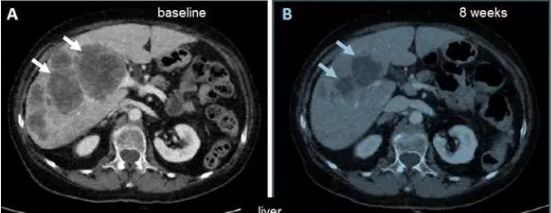

一位75岁女性患有转移性结直肠癌(CRC)患者非常幸运:

• 原发性结肠肿瘤。

• 腹膜癌病。

• 肝转移。

每周口服1600mg / m 2恩曲替尼一周一次,连续4天(即4天/ 3天休息),每28天连续三周。治疗八周后,病灶明显缩小。

肝转移瘤明显萎缩